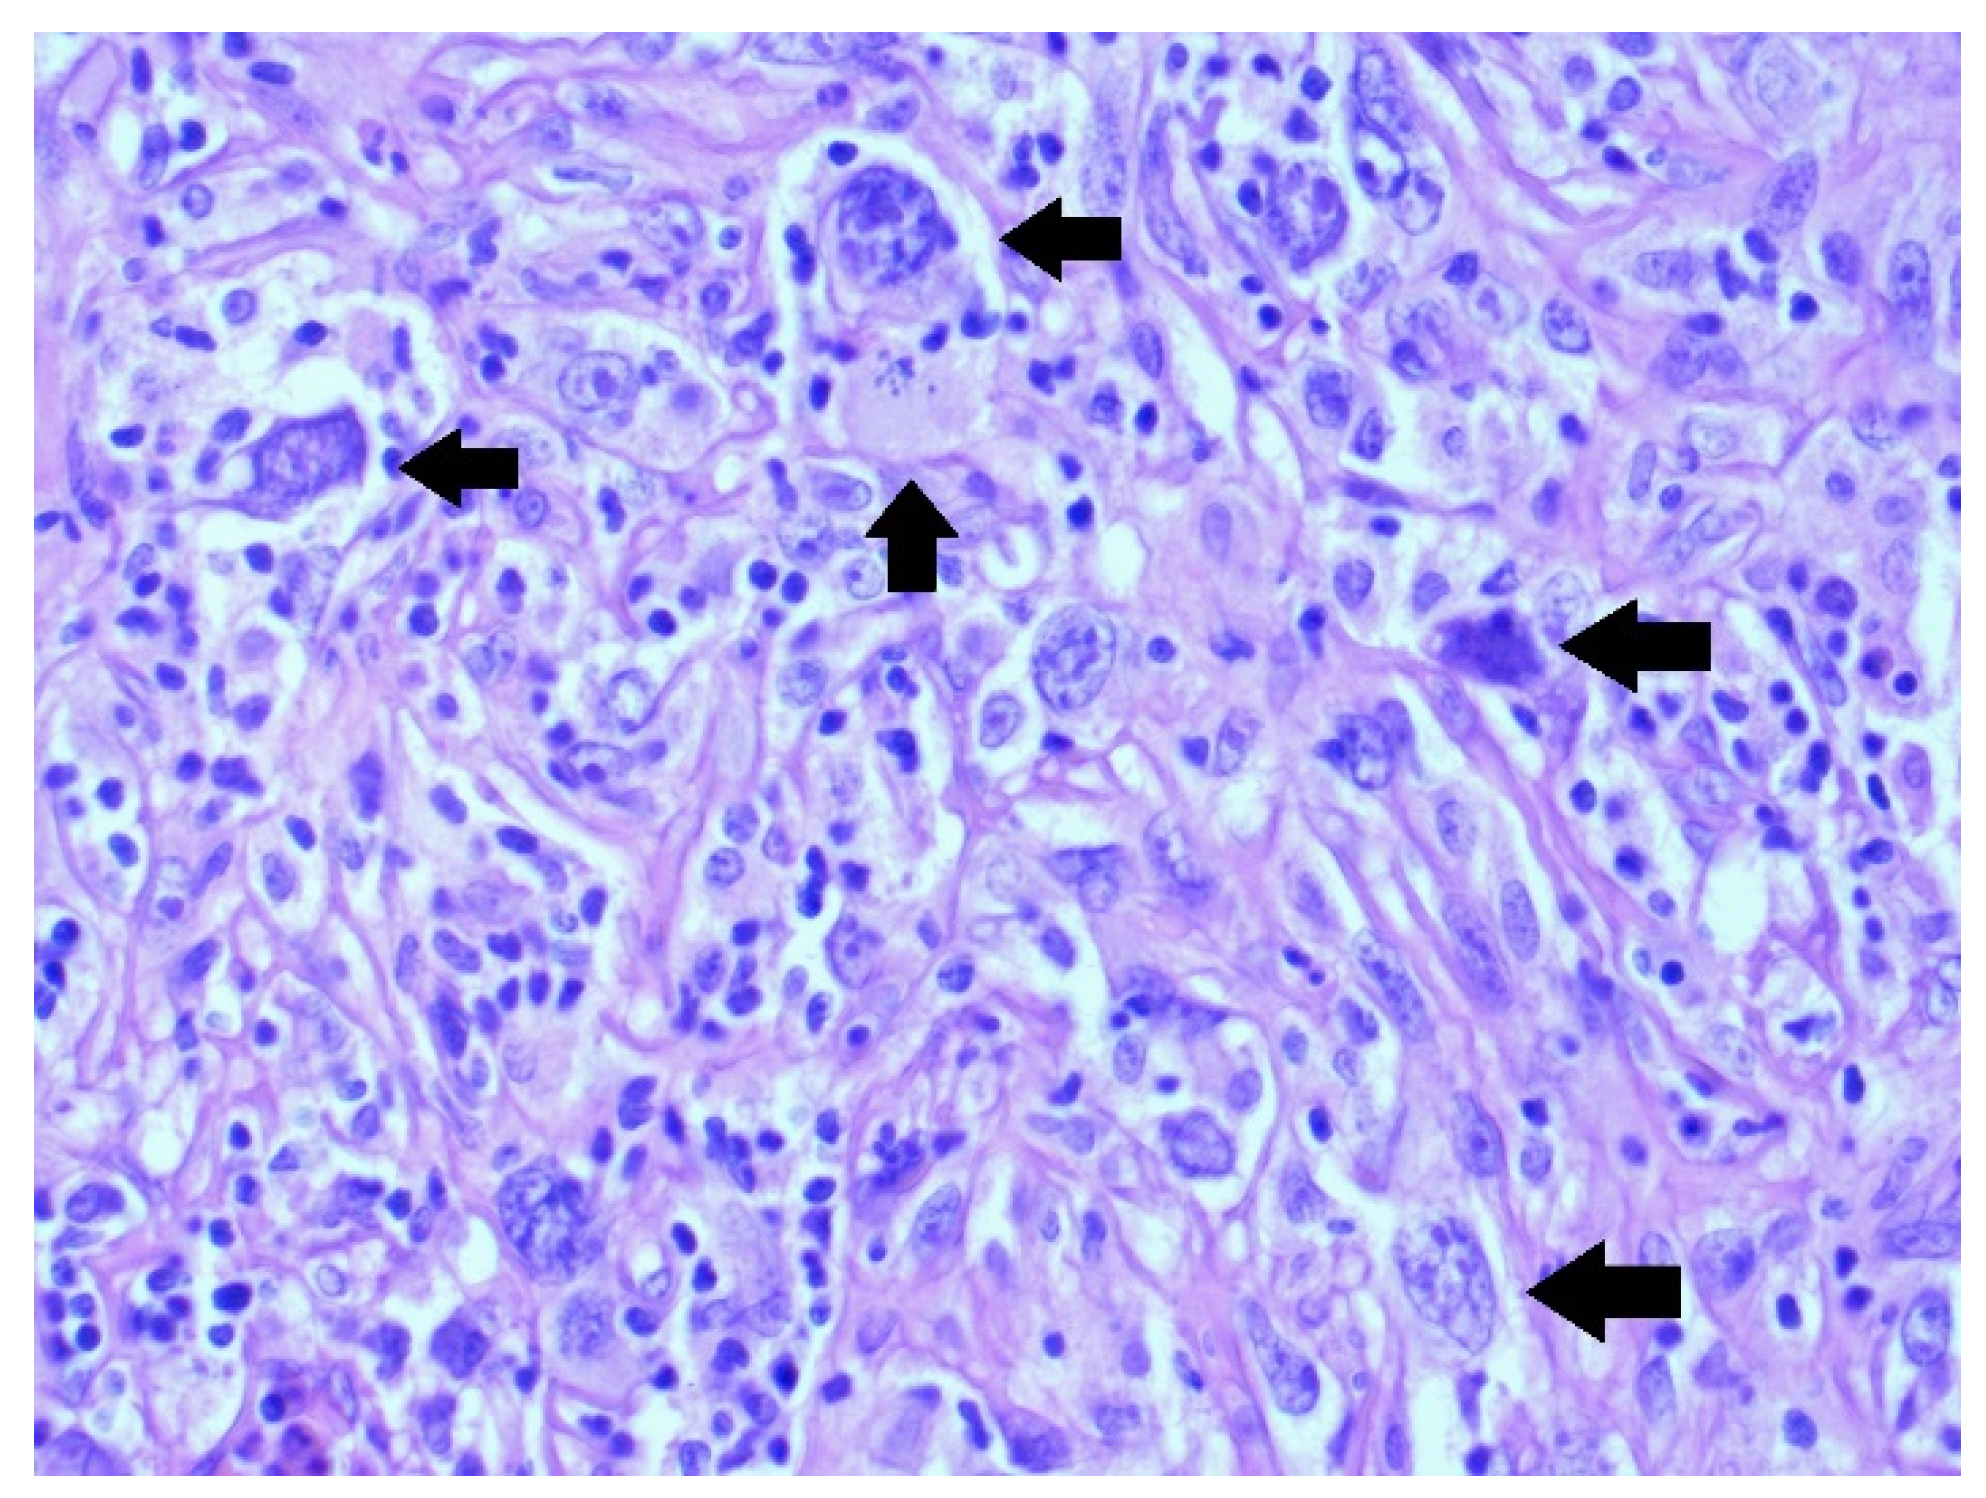

- Histopathology: complete investigation and extensive immunohistochemistry tests are necessary.